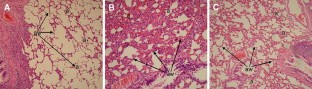

The organ that is affected first and most severely in intraabdominal sepsis is the lung. Oxygen radicals and active neutrophils in the lung are important sources for severe pulmonary inflammation leading to acute lung injury (ALI)/acute respiratory distress syndrome. The aim of this study was to investigate the effects of leflunomide, an immunomodulatory agent, on oxidant/antioxidant status with nitric oxide (NO) level and myeloperoxidase (MPO) activity in rats with sepsis-induced ALI. Fifty male Wistar albino rats were divided into five groups: control, sham, sepsis, leflunomide (10 mg/kg, intragastrically for two doses with an 8 h interval prior to the experiment) and sepsis + leflunomide. After the animals were anesthetized with ketamine and xylazine, the abdominal cavity was opened and ligated just below the ileocaecal valve with 3–0 silk. The antimesentric surface of the cecum was perforated and the cecum was gently compressed until fecal matter was extruded to induce sepsis. None of the rats received antibiotics during the experimental procedures. The experiment was ended 24 h after cecal ligation puncture (CLP) with the cervical dislocation under anesthesia. The lung tissues were removed for analysis of biochemical parameters and light microscopic investigation. The lung superoxide dismutase (SOD), catalase and glutathione peroxidase activities were decreased in the sepsis group as compared to the group control, sham, leflunomide and sepsis + leflunomide (P < 0.05), and SOD activity were significantly higher in group sepsis + leflunomide than sham, control, leflunomide and sepsis group (P < 0.05). The lung MPO, malondialdehyde (MDA), protein carbonyl and NO levels were higher in the sepsis group when compared to group control, sham, leflunomide and sepsis + leflunomide (P < 0.05), and MPO, MDA and NO levels were higher in the sepsis + leflunomide group than in the sham, control and leflunomide group (P < 0.05). The light microscopic evaluation showed that pulmonary architecture was preserved, and infiltration of neutrophil and edema decreased in sepsis + leflunomide group. The grade of alveolar damage was significantly decreased in sepsis + leflunomide group in comparison with sepsis group (P < 0.05). Our findings suggested that leflunomide attenuated the lung injury after CLP-induced sepsis by inhibition of neutrophils accumulation and increasing endogenous antioxidant capacity.